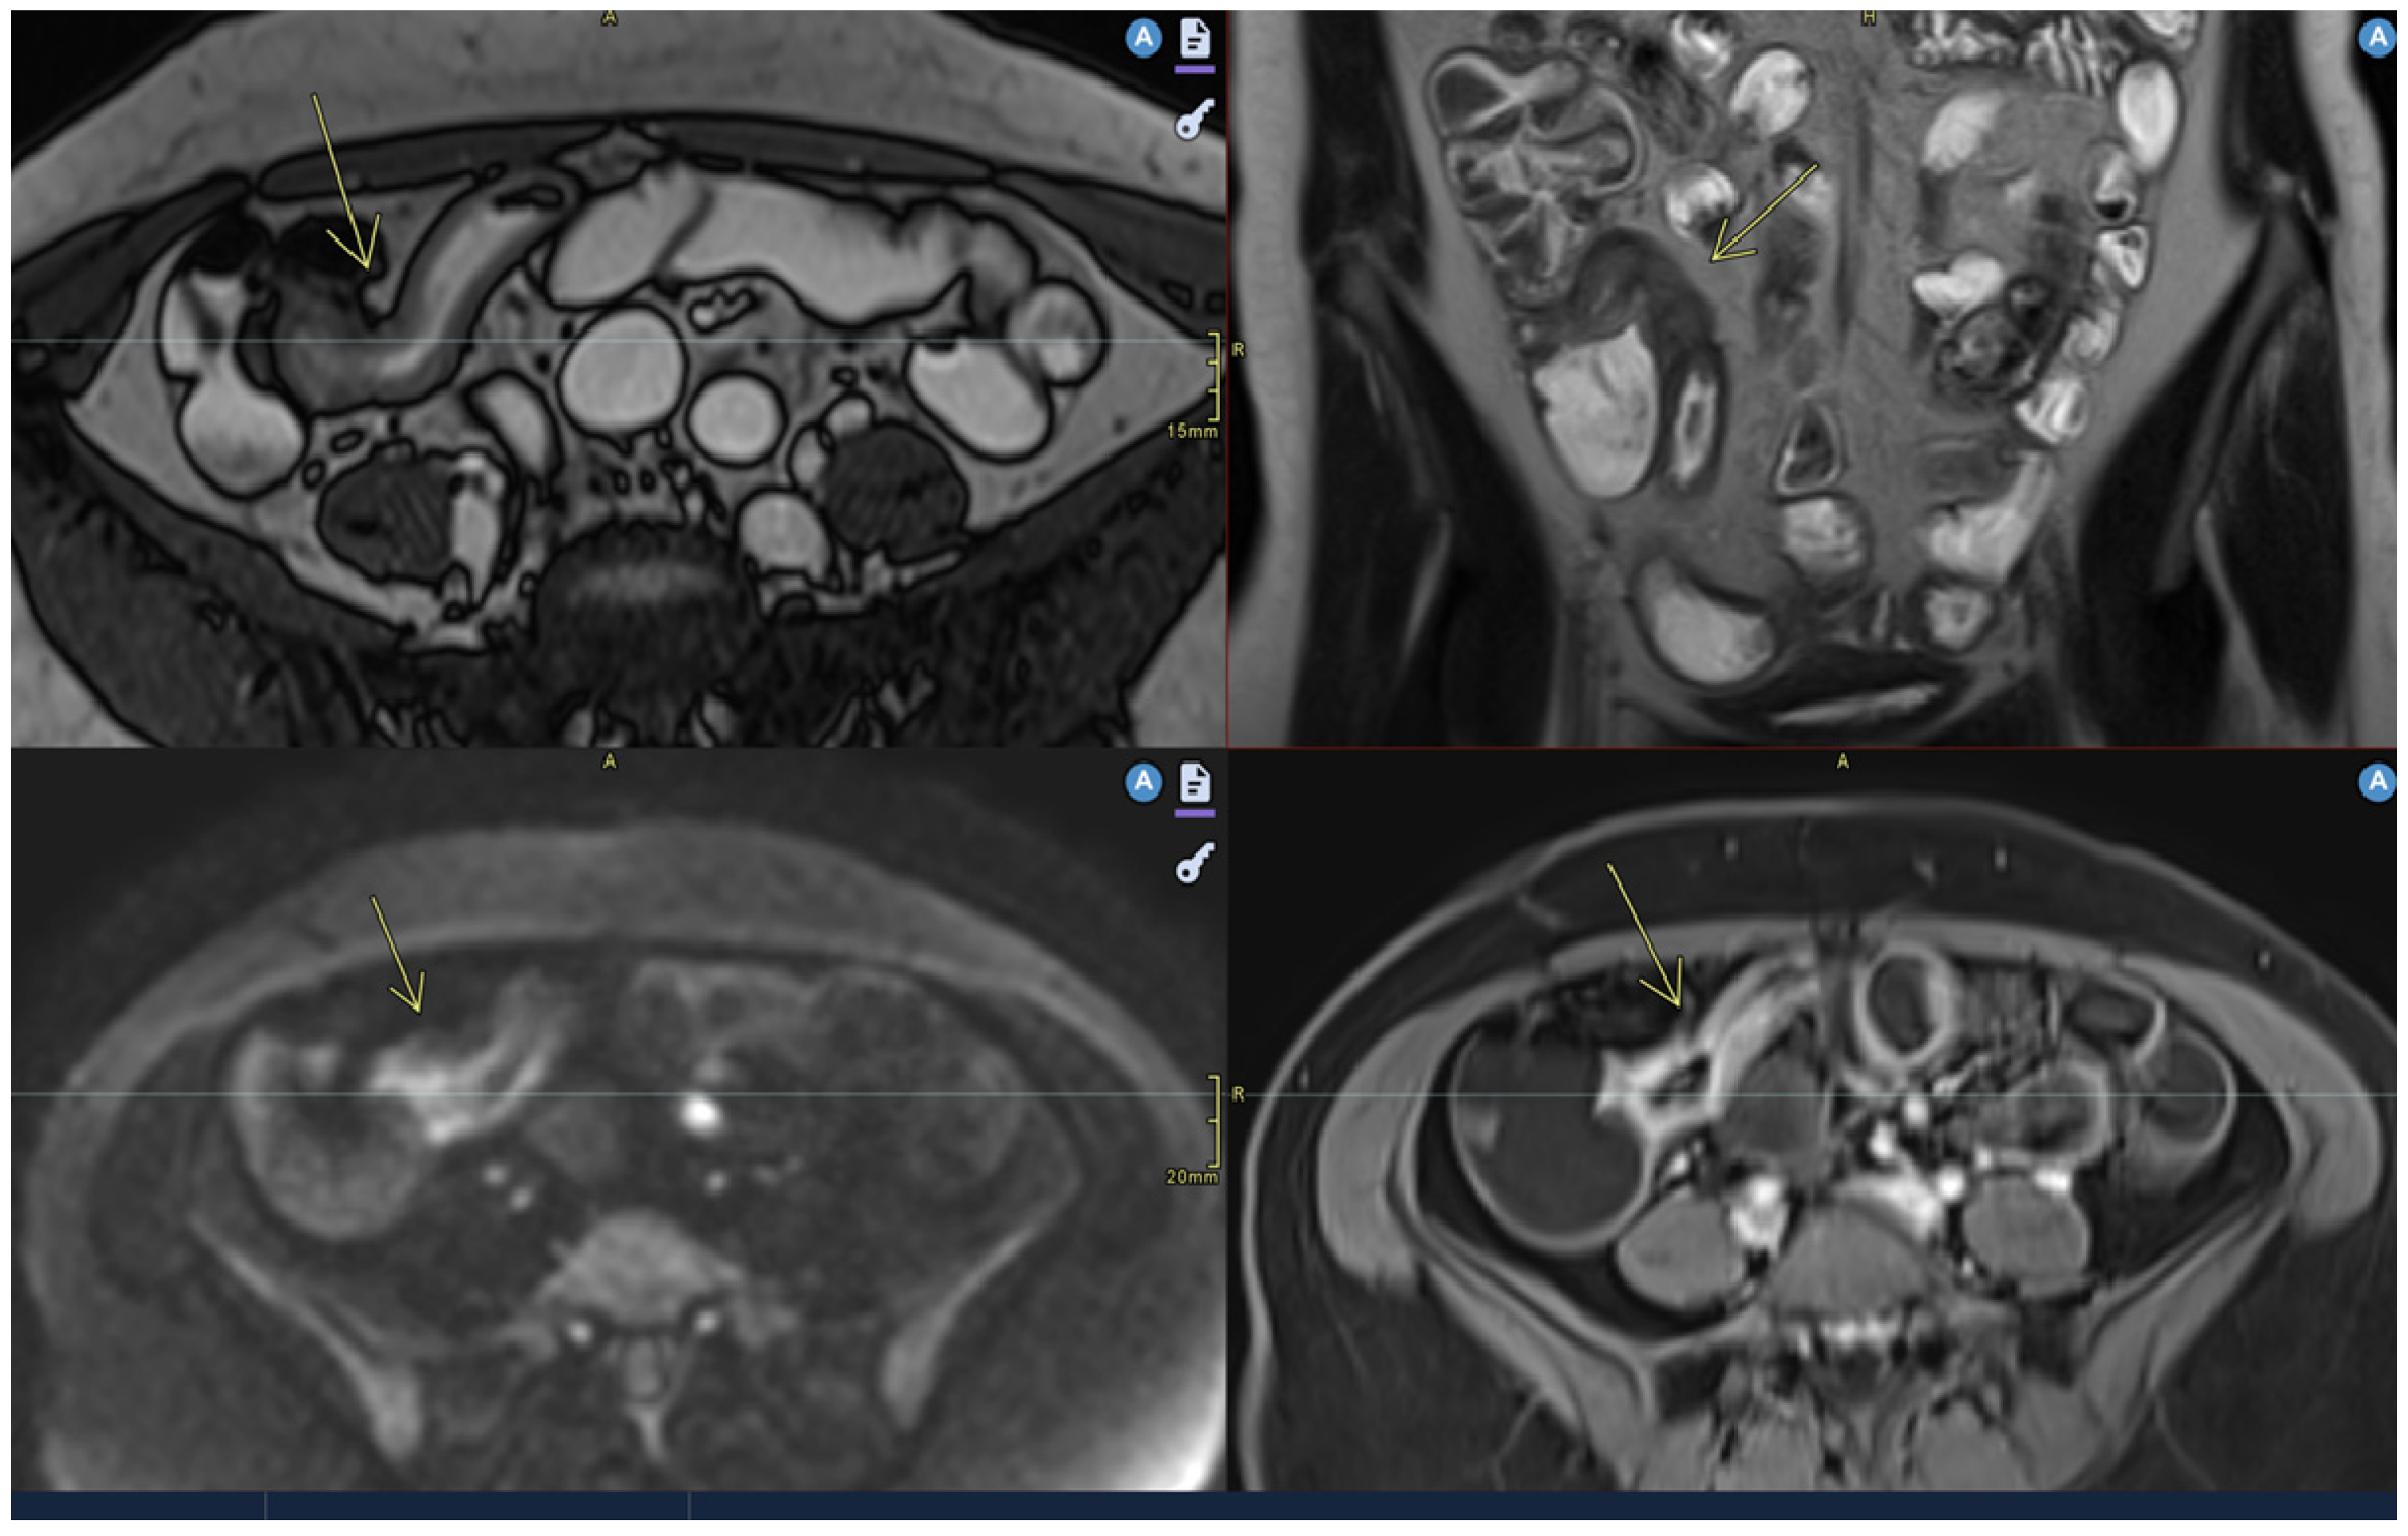

- Mural thickening:

- Can be mild (<5 mm), moderate (<9 mm),orsevere (>10 mm).

- Commonly occurs in active areas of inflammation (Figure 1).